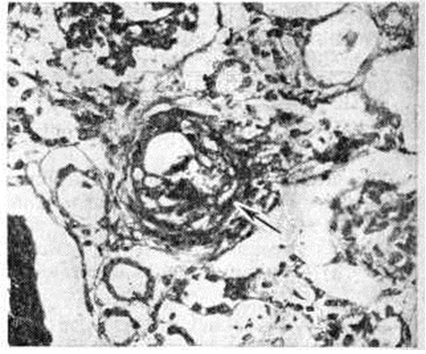

Рис. 2.

Микропрепарат почки при болезни Мошкович: почечный клубочек (указан стрелкой) с участками фибриноидного некроза (I), окклюзией просветов капиллярных петель (2) эозинофильными массами и скоплением гематоксилинофильных ложноизвестковых зёрен (3); окраска гематоксилин-эозином, × 200.

При длительности заболевания более 2 месяцев наряду с фибриноидными изменениями выражены пролиферативные и склеротические. Гематоксилинофильные зернистые массы в сосудах, дающие отрицательную реакцию Коссы на известь и названные Прокшом и Томси (P. Proks, F. Tomsi, 1955) ложноизвестковыми зёрнами, могут быть скоплением микробов или продуктами гемолиза. Они часто встречаются в капиллярах почечных клубочков наряду с фибриноидным некрозом капиллярных петель и окклюзией их эозинофильными массами (рис, 2). В печени, почках, селезёнке, костном мозге, лимфатических, узлах с помощью реакции Перльса обнаруживают скопления гемосидерина. В костном мозге п селезёнке количество плазматических клеток увеличено.